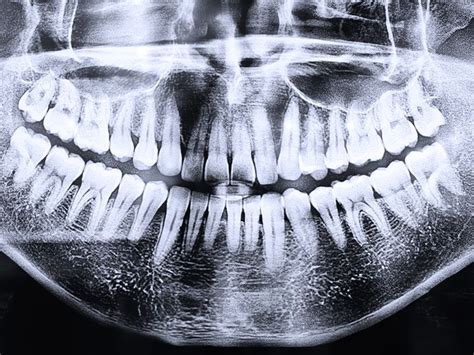

En los tratamientos de ortodoncia, las pruebas radiológicas se utilizan con frecuencia para diagnosticar patologías relacionadas con los dientes. Por ejemplo, la radiografía panorámica y la telerradiografía del cráneo son dos de las pruebas más importantes. Entre muchas otras cosas, permiten observar la posición y la forma de los dientes y la mandíbula o valorar las raíces de las muelas. Esto servirá para indicar el tratamiento de ortodoncia adecuado. Las radiografías también se utilizan cuando es necesario analizar el desgaste y la pérdida de hueso dental en la mandíbula.

Las radiografías panorámicas y telerradiografías laterales son dos de las pruebas más importantes para diagnosticar problemas que deben tratarse con ortodoncia. A través de la radiografía el ortodoncista puede encontrar las patologías pertinentes, pero también observar la posición y la forma de dientes y mandíbula.

- Panorámicas: Ofrecen una visión completa de los dientes, maxilares y mandíbula en una sola imagen.